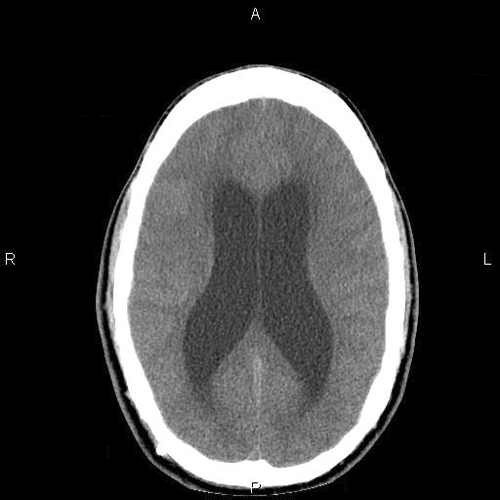

A poorly defined lesion is identified in the pineal region of the CT scan. The increased density suggest calcifications (Panel A). A moderate degree of hydrocephalus is also present (Panel B).

On MRI studies, pineal germinomas and primary pineal tumors are usually isointense to gray matter on T1-weighted, are slightly hyperintense on T2, and have strong homogenous enhancement. Intratmuoral cysts can occur as well. CT scan shows the lesion as a hyperdense mass that surrounds a calcified pineal gland. The neuroimaging characteristics of germinomas and nongerminomatous germ cell tumors are similar enough to limit diagnostic certainty, and either tissue confirmation or the measurement of specific tumor markers is needed for diagnosis. Pineal calcification on plain radiographs, uncommon in children less than 10 years of age, is a useful clue to the diagnosis of a germ cell tumor, since approximately 70% of patients with pineal region tumors have calcifications 1. The calcifications in germinoma surround the pineal gland as the germinoma grows. In contrast, pineocytomas commonly have intratumoral calcifications. Unlike germinomas, teratomas typically have heterogenous MRI signals because they can contain tissue from all 3 germinal layers.